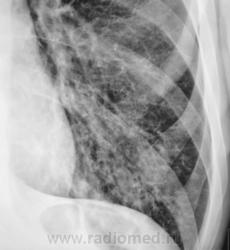

Пациент направлен на рентгенографию ОГК с диагнозом - "Левостороняя пневмония".

Анамнез стандартный. Ранее неоднократно страдал обострениями хронического бронхита. Сейчас вот не нашутку занемог - температура до 38, откашливает мокроту, кашель продуктивный.

Диагноз левосторонней нижнедолевой С10, С9 сементарной пневмонии наверное будет верным, а с учётом фона- с наличием бронхоэктазов.